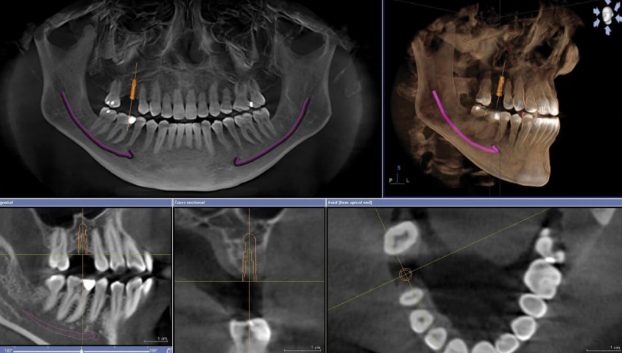

- CBCT (Cone Beam Computed Tomography): Provides 3D visualization of bone volume, density, and vital anatomical structures

Digital Planning Process

- Data acquisition:

- High-resolution CBCT (0.25mm voxel size) captured bone anatomy

- Intraoral scanning documented existing dentition and soft tissue contours

- Facial scanning incorporated for esthetic planning

- Treatment planning:

- Virtual extraction of non-restorable teeth

- Strategic positioning of six implants per arch following “All-on-X” protocol

- Verification of adequate bone volume and identification of anatomical limitations